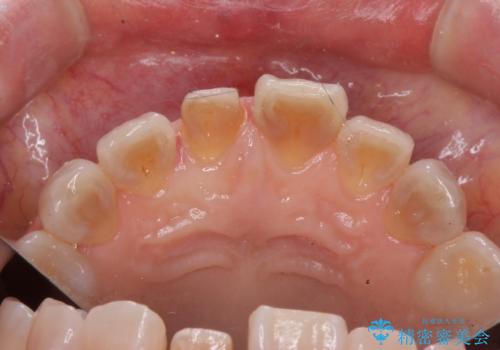

- 転倒し前歯を地面に強打して折れたとのことで来院。

幸い神経は生きており、セラミックでかぶせることになりました。

テトラサイクリン歯といって縞模様の強い歯の色調再現を行いました。

まず保険治療でコンポジットレジン修復を行い、神経の状態を確認した後、クラウンによる修復を行いました。